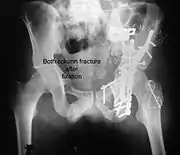

Both column fracture after fixation with screws and plates

Combined both column fractures | These are the most complex injuries. Here the weight bearing roof or dome of the acetabulum is a floating piece. This adds to complexity of management.

All three x-ray views plus CT scan is a must for diagnosis and management of this complex injury.

Like any other acetabular fracture, if the femoral head is dislocated out of the socket, early reduction into socket is a priority. However, in this injury, non-operative treatment rarely gives satisfactory results. Surgical management is ideal. The choice of approach rests with the surgeon, but going from front, or anterior approach is must. The posterior injury may be tacked with anterior approach by experienced surgeon. If the patient is unfit to undergo major surgery due to any reason, longitudinal traction to achieve secondary congruence of hip may help to restore hip function, though partially. |